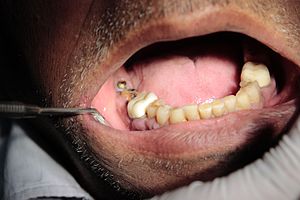

C. Extraction: the removal of a tooth. This typically is executed on teeth which are difficult, diseased, or redundant (that is the case for wisdom enamel that don't have any area to grow at the modern-day jaw). They’re commonly eliminated through pulling or cutting. A few even have their expertise tooth removed earlier than they erupt and develop problematic.

The handiest form of this dental surgery process, teeth pulling, is one of the most common offerings of the dentist. It could be executed with nearby (numbing your mouth) or fashionable (putting you to sleep) anesthesia. The reducing version of enamel extraction typically involves impacted understanding tooth determined beneath the gums, so surgical procedure is worried.